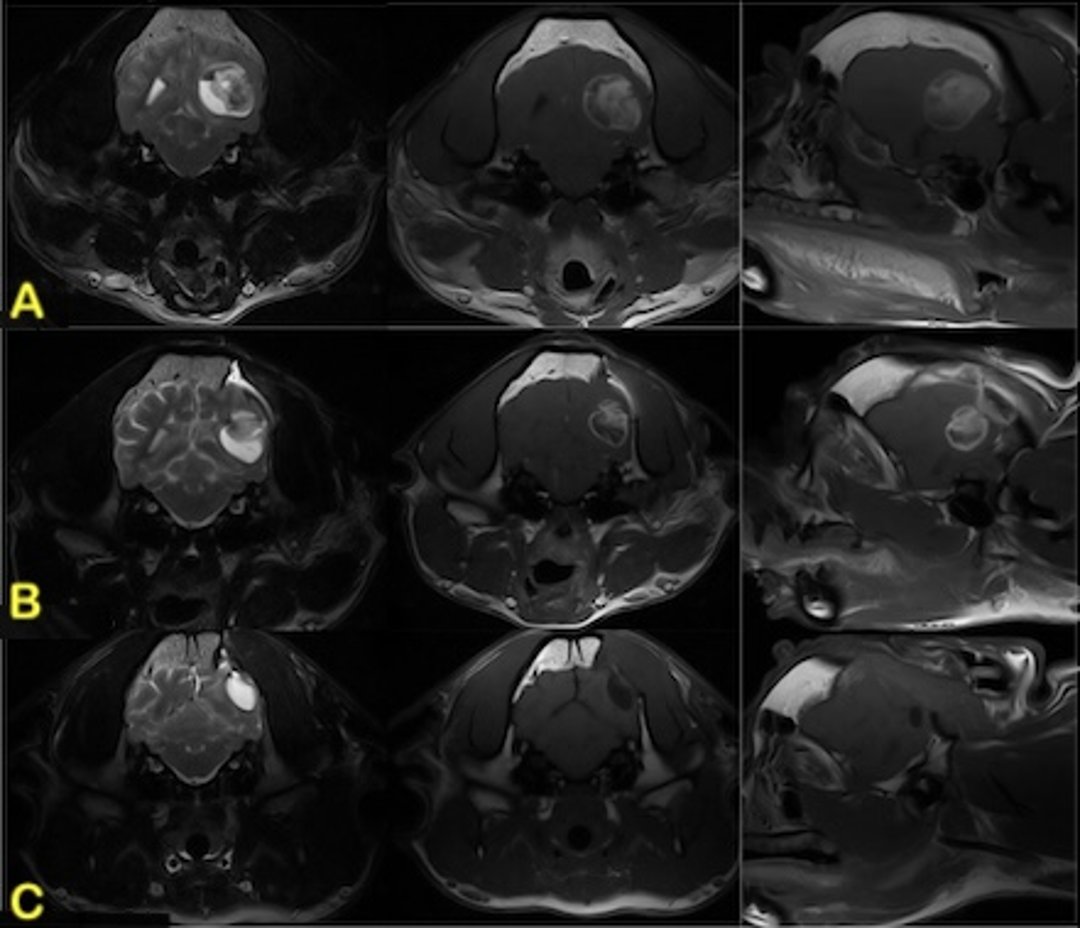

The majority of gliomas have been documented in the forebrain. Compared with astrocytomas, canine oligodendrogliomas are more likely to be T1W hypointense, associated with smooth margins, contacting the ventricles or brain surface, and distorting the ventricles, and less likely to be associated with severe peritumoral edema (3, 44, 45). Contrast enhancement is variable, but a ring-enhancing pattern, where only the periphery of the lesion enhances, is typically associated with gliomas; however, it can be associated with other lesions (eg, abscesses) as well (46).

Choroid plexus tumors) are the most common intraventricular mass lesions, and nearly 50% of canine choroid plexus tumors are associated with the fourth ventricle (47). Choroid plexus tumors are iso- to hyperintense on T1W and T2W sequences and typically demonstrate marked contrast enhancement. Dilation of the ventricular system occurs due to obstructive hydrocephalus. Choroid plexus tumors may appear as multiple intraventricular or subarachnoid contrast-enhancing masses (ie, drop metastases).

Multifocal intra-axial mass lesions are most commonly associated with hematogenous metastases of systemic neoplasms (hemangiosarcoma, carcinoma, melanoma).

MRI features of astrocytomas and oligodendrogliomas show common findings that include ringlike contrast enhancement, cystic regions within the mass, and contact with the lateral ventricle. No magnetic resonance features have been able to reliably distinguish between these two tumor types. Contrast enhancement is reportedly more common in high-grade tumors (14). (See MRI of astrocytoma, dog)

Choroid plexus tumors are well-defined, hyperdense masses with marked, uniform contrast enhancement on CT scans. Marked enhancement, potentially including hemorrhage and mineralization, is also evident with MRI (see choroid plexus tumor, MRI).